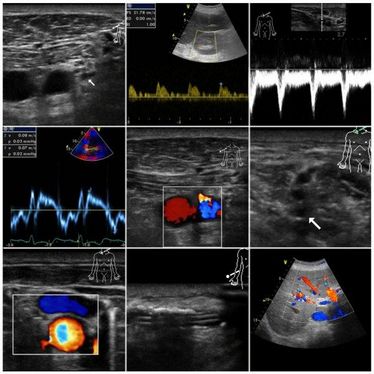

"6. Münsteraner Ultraschall-Kurs - Ultraschall in der Anästhesie" im Factory Hotel Münster

"6. Münsteraner Ultraschall-Kurs - Ultraschall in der Anästhesie" im Factory Hotel Münster

"Schwangerschaftsdiagnostik Dopplersonographie-Grundkurs" am UKM

"Schwangerschaftsdiagnostik Dopplersonographie-Grundkurs" am UKM